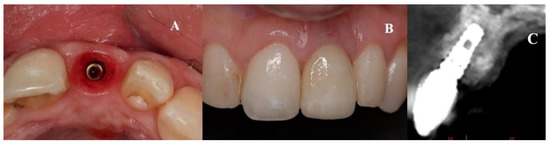

Implants were activated 6 to 10 months after placement. A temporary acrylic crown was screwed to the implant, and a temporary resin abutment (Peek® BioHorizons, Birmingham, AL, USA) was used to shape the cervical contour and emergence profile (Figure 6).

Figure 6.

(A) Initial provisionalization (adhesive bridge). (B) Subsequent customized provisionalization, screwed down to create the emergence profile.

Three months after implant activation, a screw-retained, pure porcelain crown was designed for each patient to optimize aesthetic results. The process began with the transfer of the emergence profile established with the provisional restoration. Models of the maxilla and antagonist teeth were obtained. A Ti-Base® abutment (BioHorizons, Birmingham, AL, USA) was then connected and laser treatment was used for the area of high aesthetic compromise (Figure 7).

Figure 7.

Prosthetic stage. Verification of the Zc coping on the abutment (Ti-Base® BioHorizons Birmingham, AL, USA).

The crowns were fabricated using computer-aided design/computer-aided manufacturing (CAD-CAM, Cercon® Dentsply Sirona System, York, PA, USA; Figure 8). After a mock-up to guide color determination, the mesostructure was layered with ceramic having a thermal expansion coefficient compatible with the zirconia in the mesostructure, to produce the crown. The titanium base of the abutment was then joined to the internal surface of the CAD-CAM component by applying Single Bond Universal adhesive® (3M Espe, St. Paul, MN, USA) plus RelyX Unicem® cement (3M Espe, St. Paul, MN, USA) on both surfaces, to transform the system into a single component. Through this procedure, a screw-down crown was obtained, as outlined in the treatment plan. Finally, each crown was screwed applying a torque of 32 N/cm and the palatal access was sealed with a composite of the same color as the porcelain (Figure 9). All patients followed a maintenance program (Figure 10).